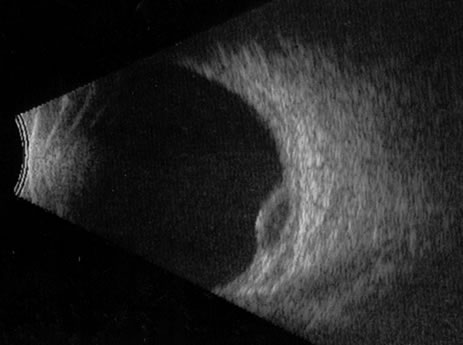

Necrotic melanomas account for approximately 5% of uveal melanomas; in the majority of cases, there is intraocular inflammation accompanying the cataract.7–9Figures 1 and 2 demonstrate a typical case. The patient had a long history of unilateral decreased vision. The eye had become painful 1 month before admission, and he was referred for evaluation of uveitis. Clinically, there was a dense, unilateral cataract with significant intraocular inflammation, which was manifested as a ciliary flush with 2+ cells and flare. Media opacity obscured all fundus detail. An immersion B-scan demonstrated a large intraocular tumor that was most consistent with a uveal melanoma. The eye was removed, and the diagnosis was confirmed histologically.10

Fig. 2. Immersion B-scan of the patient in Figure 1 demonstrates a uveal melanoma.